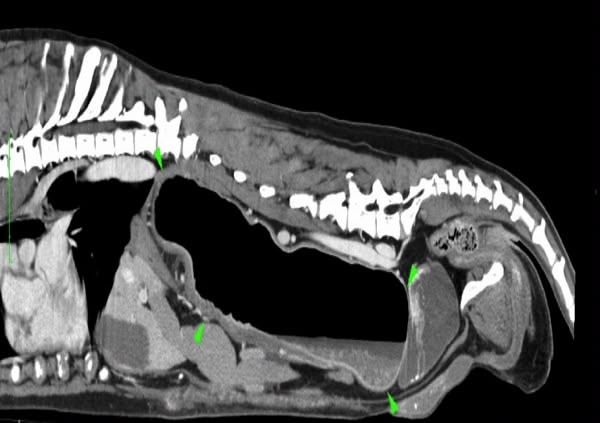

Trois cas résultent de l'extension d'une otite. Ces patients étaient présentés pour ataxie et l'un d'entre eux présentait également des crises convulsives partielles. Dans les trois cas, un examen scanner a mis en évidence une otite moyenne associée à une lésion intracrânienne extra-axiale adjacente, évoquant un empyème méningé. Dans le premier cas, un traitement antibiotique probabiliste permet la résolution des signes cliniques. Dans le deuxième cas, des prélèvements par vidéo-otoscopie permet d'identifier la présence de Staphylococcus felis. Un traitement antibiotique ciblé entraîne la résolution des signes cliniques. Dans le troisième cas, l'examen vidéo-otoscopique permet l'identification de Pseudomonas spp. Malgré une antibiothérapie adaptée, l'état clinique du patient se détériore. Un nouvel examen scanner montre une aggravation de l'empyème méningé. Une craniotomie est réalisée et permet le débridement de l'empyème. Cette intervention, associée à une corticothérapie et la poursuite de l'antibiothérapie, permettent la résolution des signes cliniques.

Nous présentons également un cas d'extension d'une rhino-sinusite infectieuse chez un chat présentant une ataxie. Un scanner montre des lésions naso-sinusales agressives avec lyse de la paroi sinusale frontale et empyème méningé adjacent. Une trépanation du sinus frontal permet de réaliser des prélèvements pour analyses bactériologiques et mycologiques. Un traitement antibiotique ciblé permet une bonne évolution clinique.

Le dernier cas de notre étude est un chat présenté pour ataxie et dont le scanner montre une fracture ponctiforme de l'os pariétal gauche du crâne avec abcès intracrânien et sous-cutané, probablement secondaires à un traumatisme. Un traitement médical est mis en place. Après une amélioration transitoire de son état général, le patient décède trois jours plus tard.

De ce fait, les examens d'imagerie en coupes sont essentiels pour diagnostiquer les abcès intracrâniens. Nous rapportons leur aspect au scanner mais détaillons également leurs caractéristiques à l'examen d'IRM.